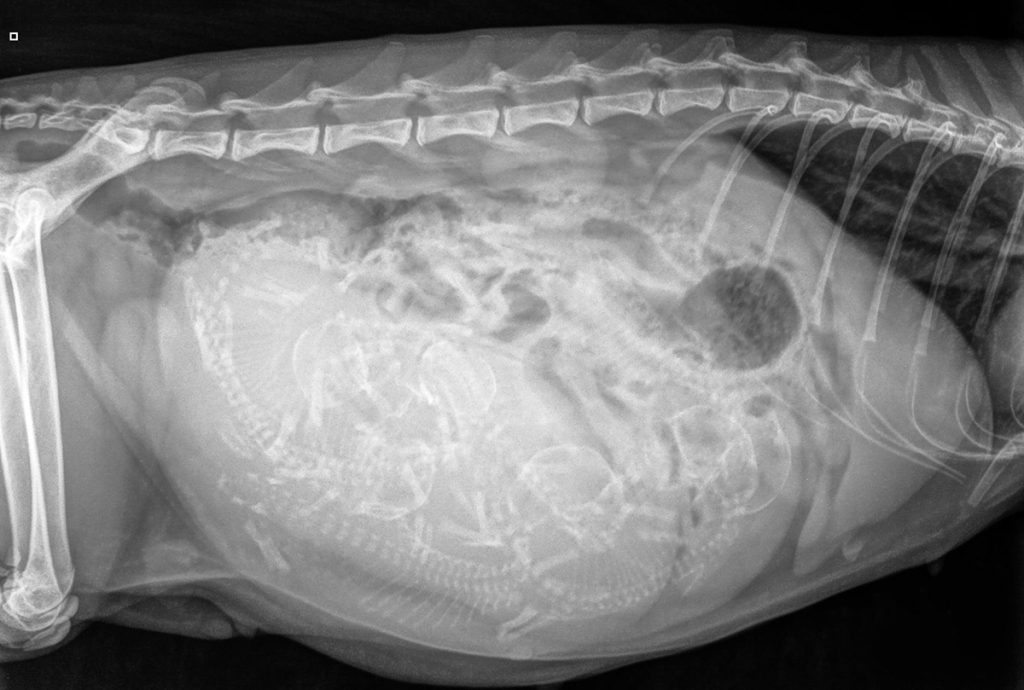

Het maken van een röntgenfoto van de buik ter bevestiging van dracht kan vanaf dag 45 van de dracht, hoewel iets langer wachten vaak een nog betrouwbaardere uitslag geeft. Dit komt omdat een röntgenfoto de skeletten van de pups en kittens in beeld brengt en deze skeletten vóór dag 45 nog uit kraakbeen bestaan i.p.v. bot, waardoor ze niet zichtbaar zijn op röntgenfoto’s. In dit stadium van de dracht is het maken van een röntgenfoto redelijk veilig voor de foetussen.

Naast bevestigen van de dracht heeft de röntgen als voordeel dat het aantal te verwachten pups kittens betrouwbaarder te bepalen is. Dit is fijn om te weten voordat de bevalling (partus) plaatsvindt, zodat het duidelijk is dat het moederdier klaar is met de bevalling, maar ook hoeveel pups of kittens u kunt aanbieden aan geïnteresseerden. Verder, wanneer er op de röntgenfoto sprake blijkt van één- of tweelingdracht bestaat het risico dat de foetussen te groot worden. Er zal dan mogelijk eerder ingegrepen moeten worden middels een keizersnede, als de partus nog niet rond de verwachte datum heeft plaatsgevonden.